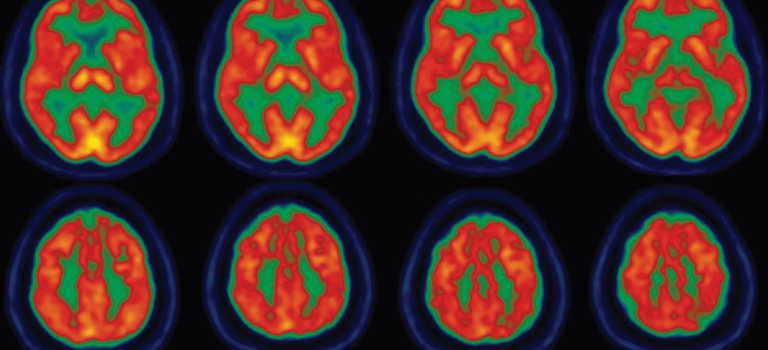

With conditions such as Parkinson’s disease (PD), tremor, dystonia, and tics, collaboration with a movement disorders specialist is key. Our experts understand your symptoms and can offer a comprehensive approach to optimize your functioning. We see the bigger picture and emphasize a partnership with you and your family.

There’s always time for second opinions when considering the treatment best for you. Our customized frameless deep brain stimulation (DBS) technique allows for shorter surgery time and greater patient comfort. We also offer novel non-invasive stimulation for tremor and highly effective Botox injections for dystonia, as well as clinical trial opportunities.